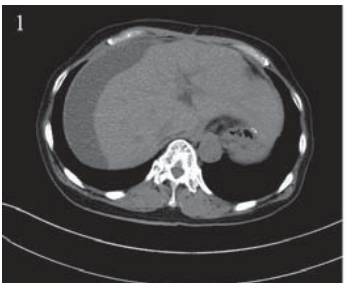

患者,女,66岁。2011年12月因“进食哽噎3 月余”就诊,查胃镜:贲门大弯后壁可见一大小约 3.5 cm×3.9 cm的不规则溃疡,周边堤样隆起。全 身CT等检查提示无其他部位转移,遂于2011年12 月22日在上海中山医院行贲门癌根治术,术中探 查见贲门部病灶,约3 cm×4 cm,质地中等,周围 脏器未见异常,遂行贲门癌根治术,食管胃机械 吻合。术后病理:“贲门”溃疡型腺癌,Ⅱ~Ⅲ级, 侵及胃壁全层及周围脂肪组织,淋巴结(3/20) 见癌转移。TNM分期为:ⅢB期(T4aN2M0), 术后复查CT:两肺少许间质性改变,后腹膜淋巴 结稍大,右肾上极局部形态异常,伴右肾囊肿。 2012年1月27日起予“奥沙利铂+替吉奥”化疗六周 期,期间复查CT无转移依据。2012年8月再次复 查CT:左肺叶间胸膜增厚,右肺上叶可疑小结 节,胃癌术后改变,肝脏小囊肿可能,肝右叶包 膜下包裹性积液,右肾上极梗死后遗改变可能, 右肾小囊肿、小结石,腹盆腔积液,见图 1。查 CA199:154.71 IU/ml,CEA:15.65 ng/ml,肿瘤 进展,遂予“紫杉醇+替吉奥”化疗一周期。2012 年11月初患者出现右上腹胀痛,进食后明显,伴 恶心、呕吐,呕吐物为胃内容物。遂入住我科。 入院查体:右上腹可触及包块,有压痛,中上腹 部可见陈旧性手术疤痕,肝区叩痛明显,余未 见异常。血常规、肝肾功能正常。CA199:143.3 IU/ml,CEA:16.56 ng/ml。腹腔B型超声:腹腔 积液,最大前后径约26 mm;肝包膜下巨大囊性 占位,大小约16.3 cm×9.5 cm,见图 2 。胸部CT未 见异常。腹盆部CT:胃癌术后改变,肝脏小囊肿 可能,肝右叶包膜下包裹性积液较前明显增加, 右肾上极梗死后遗改变可能,右肾小囊肿、小结 石,右肾轻度积水,腹盆腔积液,见图 3。

图 1 肝包膜下巨大囊性转移瘤患者腹部CT Figure 1 Abdominal CT of huge cystic metastatic tumor of hepatic subcapsular The encapsulated fluid under the right lobe of the liver capsule |